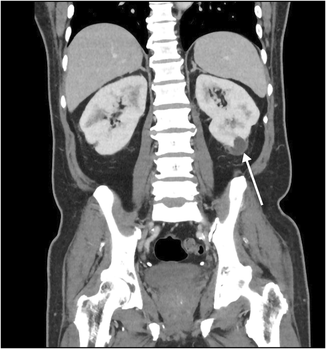

A 65‐year‐old man of Indonesian ethnicity with type 2 diabetes mellitus and hypertension first presented to a peripheral hospital in March 2023 with fevers and diabetic ketoacidosis. He was treated for urosepsis, with Klebsiella pneumoniae isolated in urine and blood cultures. Computed tomography (CT) scan showed multifocal, bilateral thickened perirenal infiltrates, which were discussed at a radiology multidisciplinary meeting and thought to be possibly due to lymphoproliferative disease (Box 1). The infectious diseases team was consulted by the treating medical team; however, as the infectious diseases team was located at the tertiary centre, they could not physically review the patient, and gave advice on antibiotic therapy and duration over the phone. The patient was treated with three days of intravenous (IV) antibiotics and discharged on oral amoxicillin with clavulanic acid, completing a 14‐day antibiotic course. Outpatient screening tests for lymphoproliferative disease and haematology follow‐up were scheduled, with a repeat CT scan planned for three months post‐discharge. Notably, a month prior to his hospital presentation, he travelled to Indonesia, where he required overnight hospital admission for haematemesis.

Box 1 – Computed tomography scan (coronal plane) showing thickened perirenal infiltrates around the kidney (arrow)